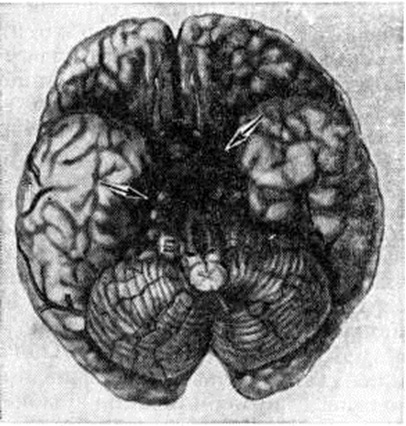

Эпидуральные и субдуральные кровоизлияния в подавляющем большинстве случаев наблюдаются при черепно-мозговой травме (смотри полный свод знаний). Субарахноидальное кровоизлияние возникает наиболее часто вследствие разрыва врождённых мешотчатых или артериовенозных аневризм (смотри полный свод знаний: Аневризма сосудов головного мозга), располагающихся чаще всего в местах разветвления сосудов основания головного мозга (рисунок 1). Некоторые инфекционные болезни, например, грипп (смотри полный свод знаний), геморрагические лихорадки (смотри полный свод знаний) и другие, при тяжёлом течении иногда могут сопровождаться Подоболочечные кровоизлияния Нередко Подоболочечные кровоизлияния возникают в пожилом возрасте у больных атеросклерозом при разрыве склерозированных сосудов мозговых оболочек, а также при хронический воспалительных процессах в твёрдой оболочке мозга, сопровождающихся поражением вен (смотри полный свод знаний: Пахименингит). Развитию Подоболочечные кровоизлияния способствуют заболевания печени, крови, авитаминозы, приводящие к развитию геморрагического синдрома. В ряде случаев Подоболочечные кровоизлияния могут сопутствовать кровоизлияниям в вещество головного мозга при гипертонической болезни, располагаясь часто в задней черепной ямке на поверхности полушарий мозжечка или ствола мозга (рисунок 2, 3). Скопление крови в задней черепной ямке нарушает отток цереброспинальной жидкости и создаёт условия для развития окклюзионной гидроцефалии (смотри полный свод знаний) и отёка мозга (смотри полный свод знаний: Отёк и набухание головного мозга). Вызвать Подоболочечные кровоизлияния могут резкие наклоны туловища, физическая нагрузка, эмоциональное напряжение, сопровождающиеся значительным подъёмом АД.

Рис. 2.

Макропрепарат головного мозга е паренхиматозно-субарахноидальным кровоизлиянием (указано стрелками).

Рис. 3.

Макропрепарат головного мозга с субарахноидальным кровоизлиянием на основании мозга: обширные участки кровоизлияния (указаны стрелками).